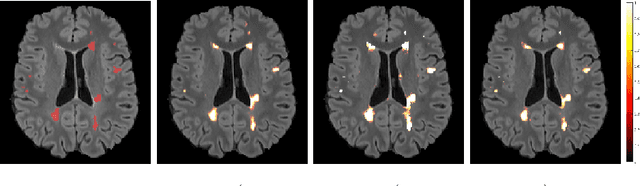

Abstract:In this work, we present a comparison of a shallow and a deep learning architecture for the automated segmentation of white matter lesions in MR images of multiple sclerosis patients. In particular, we train and test both methods on early stage disease patients, to verify their performance in challenging conditions, more similar to a clinical setting than what is typically provided in multiple sclerosis segmentation challenges. Furthermore, we evaluate a prototype naive combination of the two methods, which refines the final segmentation. All methods were trained on 32 patients, and the evaluation was performed on a pure test set of 73 cases. Results show low lesion-wise false positives (30%) for the deep learning architecture, whereas the shallow architecture yields the best Dice coefficient (63%) and volume difference (19%). Combining both shallow and deep architectures further improves the lesion-wise metrics (69% and 26% lesion-wise true and false positive rate, respectively).